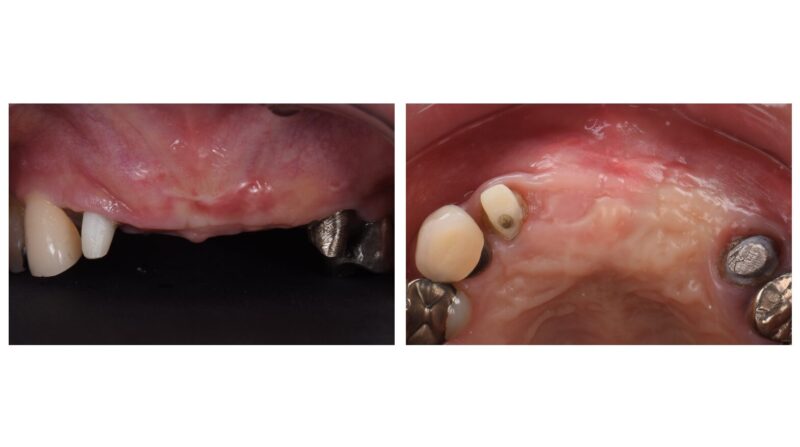

一般的に歯を抜いた後、そのまま放置すると骨や歯肉は時間とともに痩せてしまいます。(資料2〜5)

特に前歯ではこの影響が大きく、後からインプラントを入れる場合、骨を増やす処置(GBR)が必要になることも多く、治療回数や負担が増える傾向があります。